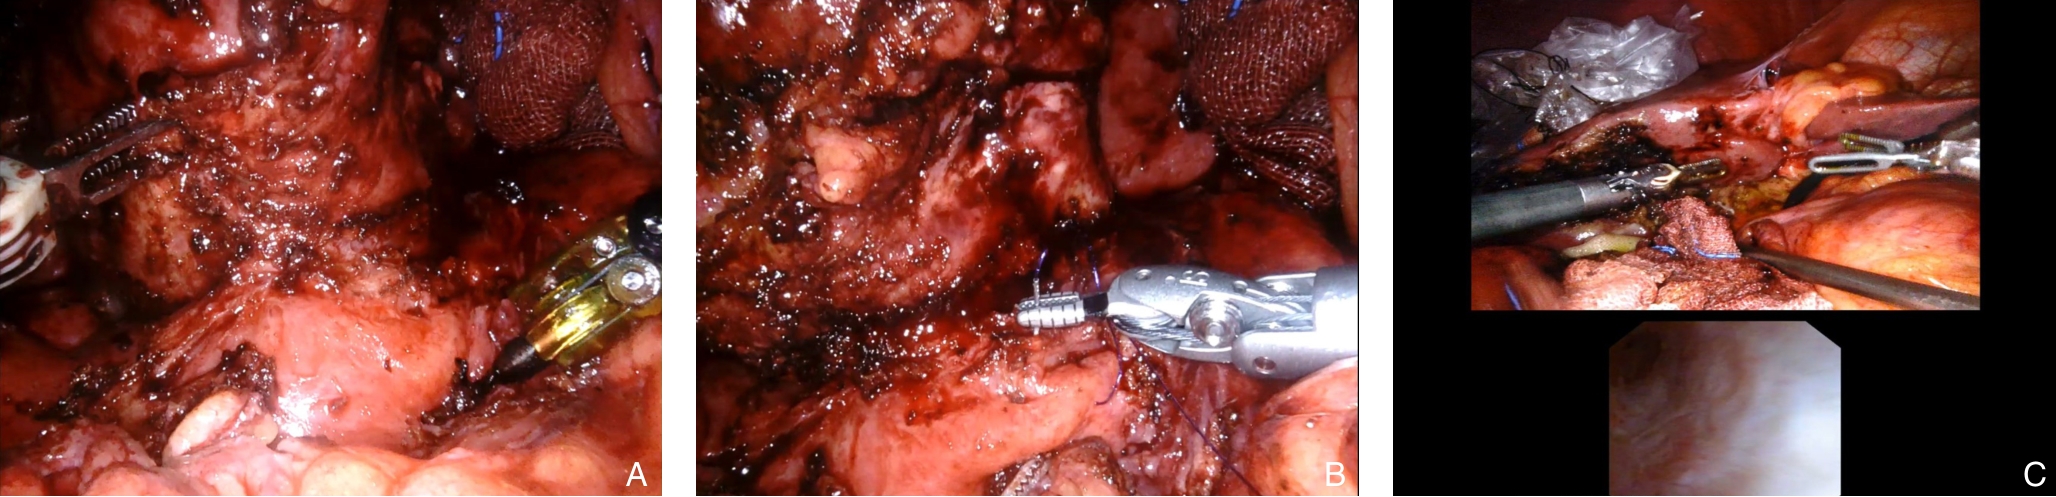

2025, 34(8):1783-1789. doi: 10.7659/j.issn.1005-6947.250076

摘要:背景与目的 肝内胆管癌(ICC)是一种起病隐匿、预后极差、初诊多为进展期的原发性肝癌,其治疗选择有限,预后差。本研究旨在探讨靶向治疗、免疫治疗与肝动脉灌注化疗(HAIC)联合应用于晚期ICC的转化治疗的潜力,为临床转化治疗提供参考。方法 回顾广东医科大学附属医院2021年11月收治的1例晚期ICC行靶向治疗、免疫治疗与HAIC联合治疗后成功转化并接受手术患者的诊治过程,并复习国内外相关文献。结果 患者为52岁男性,确诊为T2N1M0-Ⅲb期ICC。患者拒绝接受以吉西他滨联合顺铂为主的一线化疗方案,同意行靶向治疗联合免疫治疗与HAIC的综合治疗,在接受4个治疗周期后评估肿瘤达到部分缓解,具备实施根治性手术治疗的条件。患者随后接受了腹腔镜下肝S6段和部分S7段切除、胆囊切除以及肝门部和腹膜后淋巴结清扫术。术后患者规律行靶向免疫联合化疗的综合治疗方案。在疾病出现复发和转移后,化疗药物进行了相应调整。截至目前,患者无病生存期达15个月,总生存期超过3年。结论 靶向治疗、免疫治疗与HAIC三联方案可提高晚期ICC患者的转化机会并延长生存期,具有较好的安全性和临床应用前景,但其疗效仍需多中心研究进一步验证。